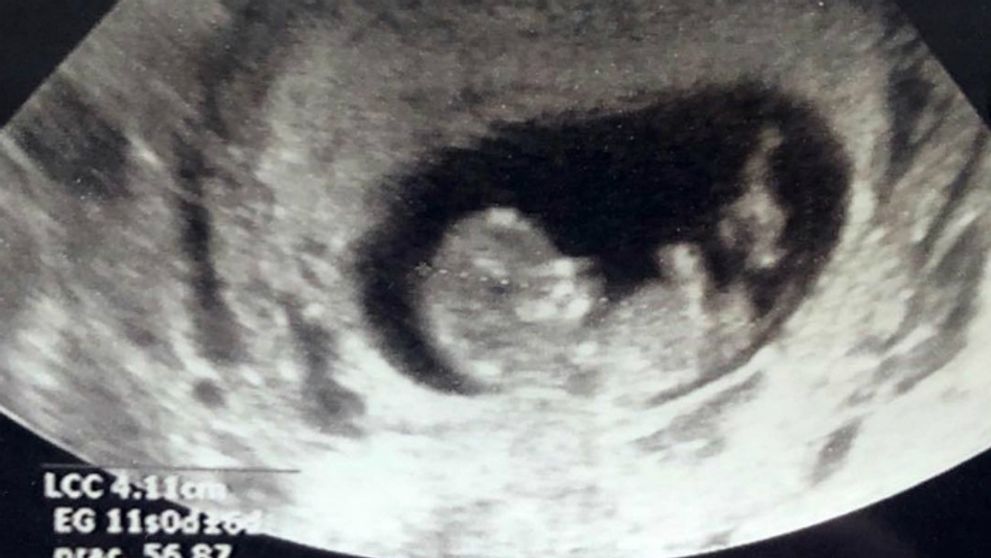

Pohlavie očakávaného potomka ešte nepoznajú.

44-ročný sympaťák sa radostnou správou, že jeho manželka, televízna moderátorka Odalys Ramirez je tehotná, pochválil na sociálnej sieti.

"Dieťa na ceste!!! Aké šťastie! Čakáme ťa s veľkou láskou. Blahoželám aj Santinovi a Gii, pretože dostanú brata alebo sestru," napísal na Instagrame.

Pre Odalys a hviezdu mexických telenoviel to bude druhé dieťa, pretože spoločne už majú tri a pol ročnú dcéra Giu. Ďalšie dieťa má Patricio zo vzťahu s herečkou Grettell Valdez, 10-ročného syna Santina.